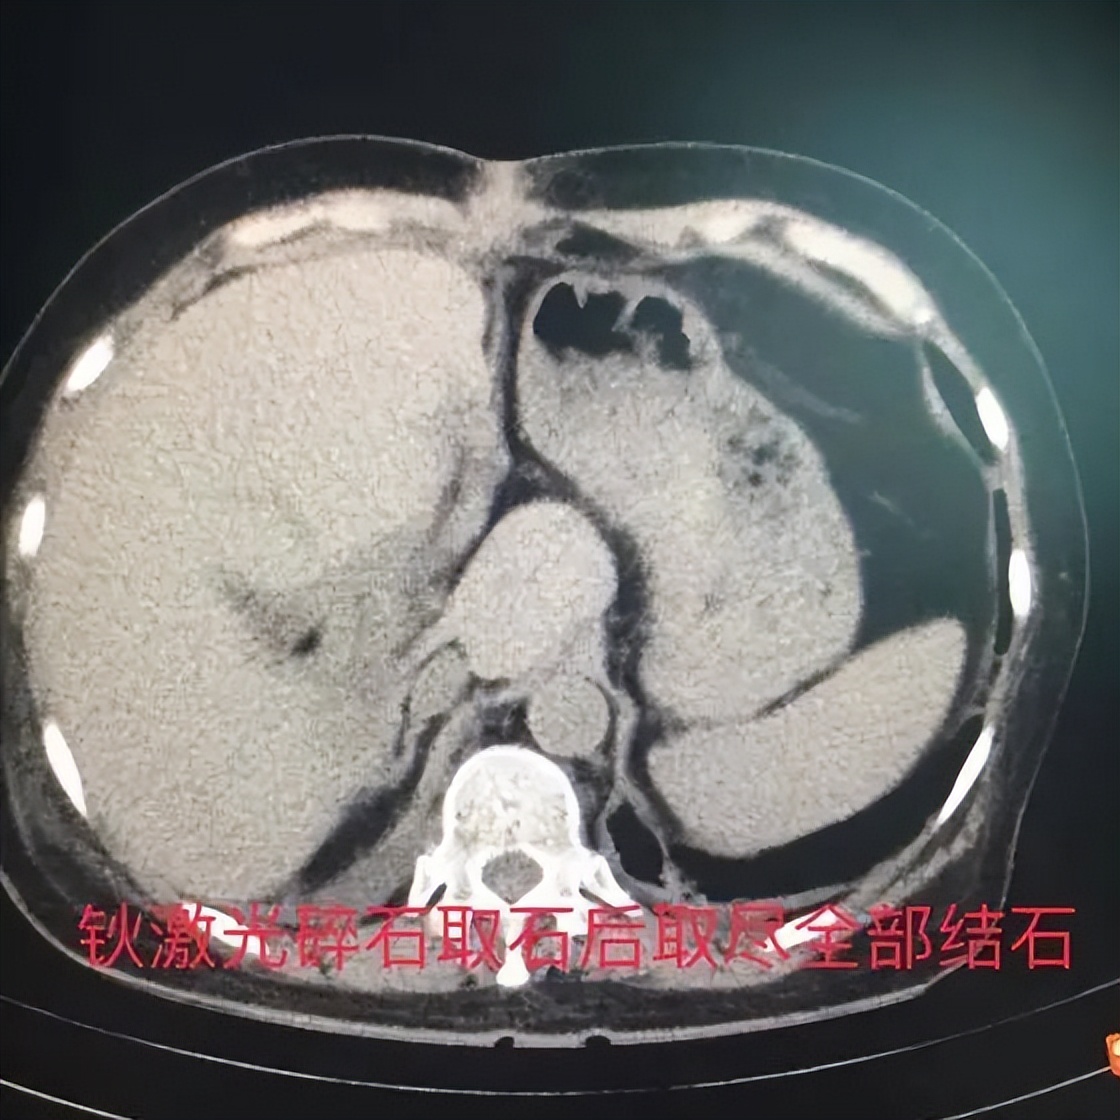

患者体质较差,恢复的也很缓慢,经过医护人员的共同努力和积极治疗,患者终于养好了伤口,恢复了体质。患者术中留置的T管窦道是以后取石的通路,虽然患者胆管水肿、糜烂并且合并一定的溃疡,且整块高密度结石嵌顿于右后肝管开口远端,矫正胆管狭窄开口过程中稍有不慎可能导致难以控制的胆道出血,但是肝胆外科的医师们还是没有放弃,在非麻醉状态下经过3次的钬激光切开狭窄、扩张右后叶胆管开口,以及碎石、取石治疗,患者终于彻底取净了肝胆管结石。每次过程都谨小慎微、安全操作,患者终获痊愈。眉头紧锁的蔡女士终于露出了久违的笑容,一双儿女也终于放心思想包袱,可以安心去外地工作了。

据实施手术的李金海医师描述,患者既往有乳腺癌、开放的腹部胆道取石和肝叶切除的手术史,且长期饱受胆管炎的痛苦,医学上属于“脆弱体质”,再次手术风险大。本身肝内胆管结石的手术又是创伤大的手术,若按传统手术理念,一次性祛除病灶、取净结石,患者往往不能耐受手术的打击。自从有了钬激光碎石设备后,在切开狭窄胆管及碎石方面的优势凸显,分次分步骤的治疗方案让患者在达到取净结石的目的同时治疗更为安全。最终,患者历经“手术关”、“取石关”,终获痊愈、如获新生,手术的成功得益于医院、科室对新技术新设备利用的重视、治疗理念的更新以及医患之间的信任。